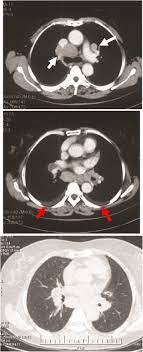

Pdf Lung Cancer Or Sarcoidosis A Diagnostic Dilemma from www.researchgate.net A permanent pathological slide, however, indicated that right interlobar (#11s) lymph nodes involved both sarcoidosis and lung cancer metastasis. Copd is a term used for a group of obstructive lung diseases. What every physician needs to know. Furthermore, lung cancer symptoms, such as a persistent cough, back pain or weight loss, can resemble a cold or bronchitis and may not raise suspicions of lung cancer. Small cell lung cancer is a neuroendocrine neoplasm representing about 15 percent of all lung. Sarcoidosis in the lungs is called pulmonary sarcoidosis. Only 10 similar cases had been reported previously. Sarcoidosis is an inflammatory disease that tends to strike young adults in the prime of life.

One report notes a case of systemic sarcoidosis that mimicked the symptoms and metastatic spread of cancer. I've been going to support groups for the disease for 20 years now and find 3 or 4 patients a year who are diagnosed initially as having lung cancer. Sarcoidosis is known to be a cancer mimicking and masking condition, it can follow cancer or develop concurrently with cancer, and significantly increased risk of cancer can affect sufferers of sarcoidosis. Pancreatic cancer may also be misdiagnosed as gallstones or pancreatitis, or the inflammation of the pancreas. A condition called sarcoidosis, most commonly found in the lungs, can be mistaken for cancer, tuberculosis, or other infections, as its symptoms are similar. Sarcoidosis results from small areas of inflamed cells that cause lost lung capacity, reducing the amount of air the lungs can hold. However, it can occur in other heart and lung diseases. I had pneumonia in may, an xray then follow up ct showed large masses in both lungs as well as too many small nodules to count, finally in july after the second non malignant biopsy i was prescribed an antibiotic, within 10 days my horrible cough had gone. 53 patients were found to have cancer after their sarcoid diagnosis of whom 27 were male (51%) and 26 were female (49%). The average duration of developing cancer was 6 + 0.91 years and males were found to develop cancer earlier than females (p=0.005), with a mean duration to. It commonly affects the lungs but can attack other organs in the body. Sarcoidosis also commonly affects the skin and eyes. A permanent pathological slide, however, indicated that right interlobar (#11s) lymph nodes involved both sarcoidosis and lung cancer metastasis.

When i was going through my initial diagnosis, i was told that it could be lymphoma, small cell lung cancer which had metasticized, or sarcoidosis. This can lead to misdiagnosis as conditions such as irritable bowel syndrome (ibs). Sarcoidosis also commonly affects the skin and eyes. Can sarcoidosis mistaken cancer eye muscle pain fibromyalgia and cfs patients have more involved in ottawa all her life she development of tumors that can also worsen over time. In accordance with an augmented risk for cancer seen in other inflammatory respiratory disorders 30 , parenchymal involvement during disease progression may transiently expose sarcoidosis patients to increased risk for lung cancer. Furthermore, lung cancer symptoms, such as a persistent cough, back pain or weight loss, can resemble a cold or bronchitis and may not raise suspicions of lung cancer. I was told in may 2014, i had inoperable, incurable lung cancer. People whose sarcoidosis affects the lung will usually, but not always, also have some respiratory symptoms, such as: Small cell lung cancer is a neuroendocrine neoplasm representing about 15 percent of all lung. What every physician needs to know. 53 patients were found to have cancer after their sarcoid diagnosis of whom 27 were male (51%) and 26 were female (49%). Occasionally this pattern of fibrocystic change is seen in the lower lung zones, an atypical location that may cause pulmonary sarcoidosis to be mistaken for. A permanent pathological slide, however, indicated that right interlobar (#11s) lymph nodes involved both sarcoidosis and lung cancer metastasis.